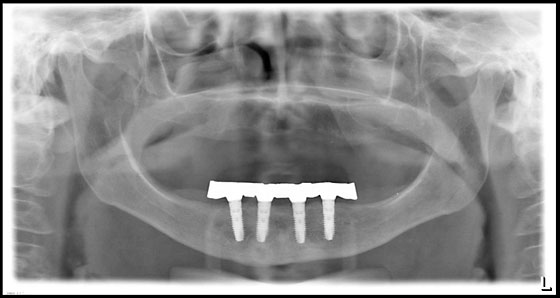

Fall: Implantatgetragene Stegarbeit bei zahnlosem Unterkiefer

Implantate Unterkiefer und vorbereiteter Abdrucklöffel

Abdrucknahme mit Positionskappen Implantate

Schematische Darstellung der Implantat- und Stegelemente

Anprobe des Stegs

OPG Steganprobe

Steganprobe

Ausgearbeiteter Steg und Anpassung der Unterkieferprothese

Eingegliederter Steg

Verlauf der Implantateinheilung bis Eingliederung Steg

Schlussbild - Implantatgetragene Unterkieferprothese